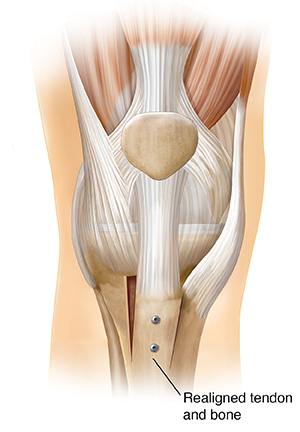

Shifting the attachment of the patellar tendon (patellar realignment)

This procedure improves tracking and is done using open surgery. Part of the tendon and the bone underneath are moved to a new location.